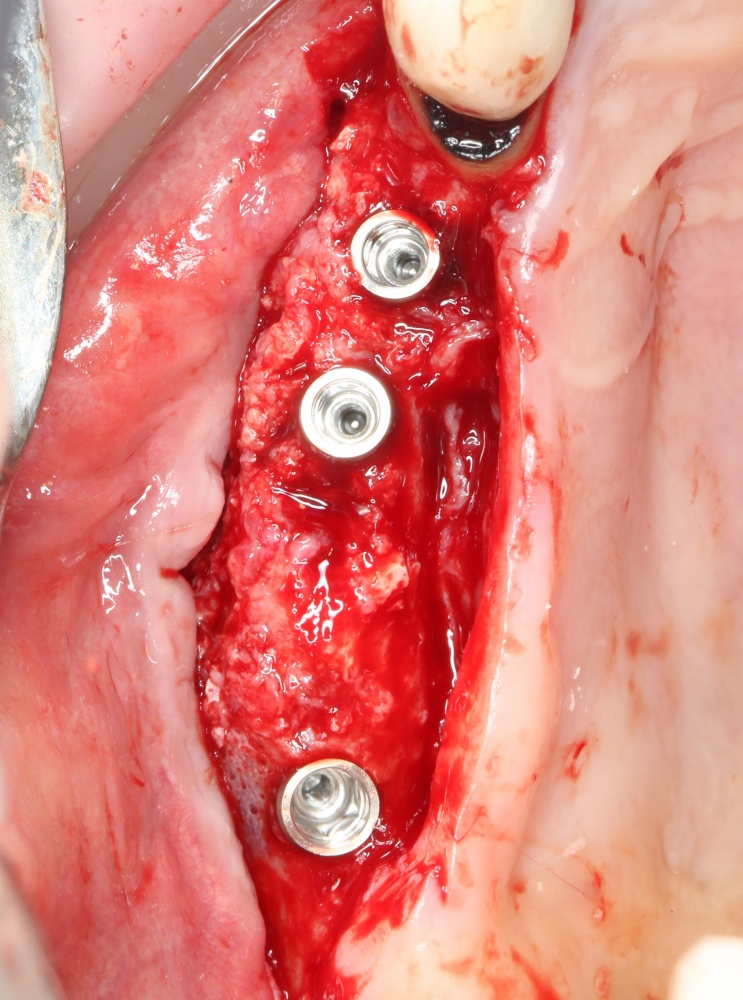

Синуслифтинг одномоментно с установкой имплантов.

Тут всё ясно и понятно. Разрез делается таким образом, чтобы удобно было поставить, в первую очередь, имплантаты, затем продляется на вестибулярную часть альвеолярного гребня для проведения синуслифтинг. Важную роль в этом играют вертикальные послабляющие разрезы и их длина:

Напомню, что подвижная слизистая оболочка может легко растянуться на 70% от своей первоначальной длины. Поэтому, моделируя вертикальный послабляющий разрез, рассеките, для начала, только кератинизированную часть десны. Обычно даже этого хватает. Далее, рассекайте подвижную слизистую оболочку по мере необходимости, пока не получите нормальный доступ к вестибулярной стенке верхней челюсти.